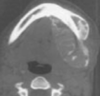

36

SMC liée à un kyste